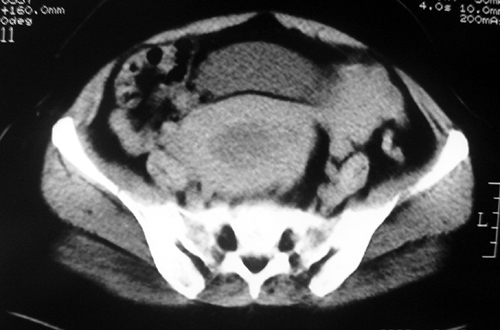

以下是引用余辉在2009-2-14 8:37:00的发言:[br]宫颈左后壁见较大低密度肿物影且向左后上方突出,宫腔内见大片状低密度区,考虑宫颈肿瘤,宫颈癌可能性大,伴宫腔积液或转移